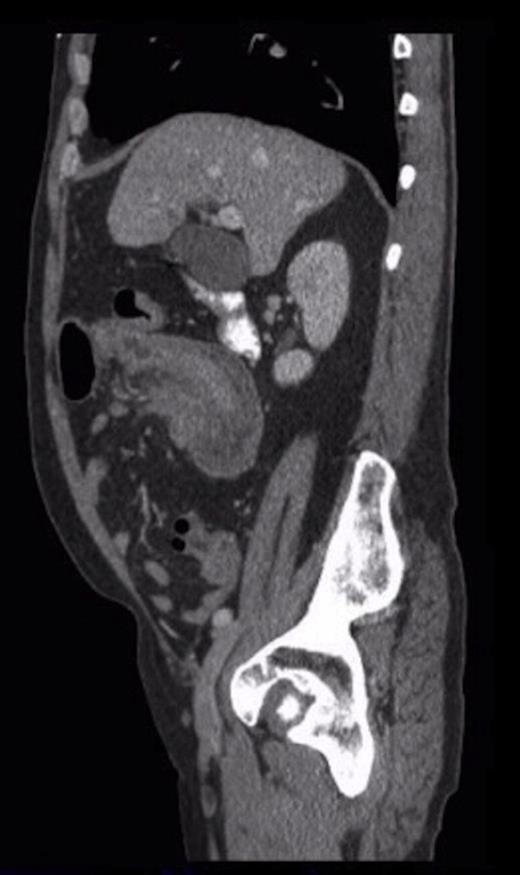

Sagittal CT showing the ‘sausage’ appearance of the intussusception

Histological analysis confirmed the presence of metastatic malignant melanoma. Biopsies contained two distinct tumours with surface ulceration spreading into the muscularis propria but with clear margins. Immunohistochemistry showed the cells to be HMB45 positive. Slides from right axillary block dissection of the metastatic melanoma were reviewed and showed similar morphology.